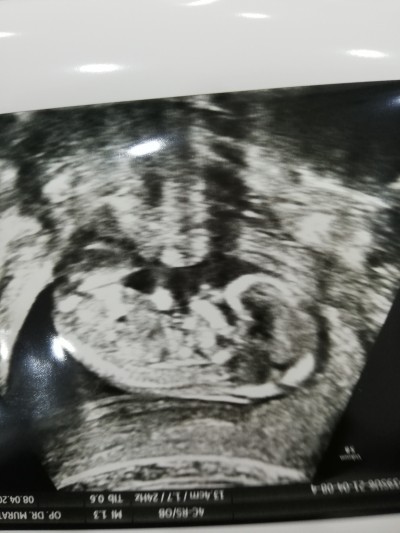

Kızlar tahmin lütfen anlayan varsa

Ama daha küçük kuzum ... Kaç haftalık?

Küçük degıl aslında 14 haftalık :)

İçime erkek doğdu doktor bir tahminde bulundu mu

Erken dıyor yapmıyor